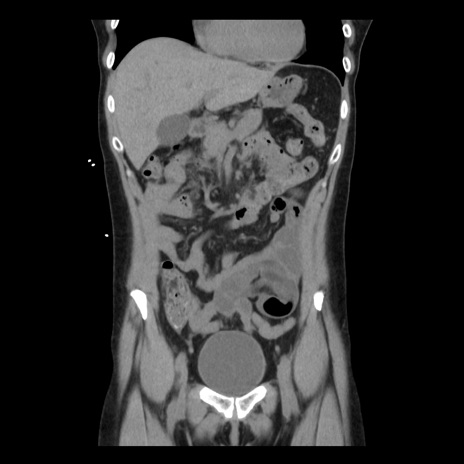

症例10(冠状断像)

【症例】 50歳代女性

【主訴】 腹痛

【現病歴】前日生レバーを食べた。今朝に排便あり。 昼前に突然発症の腹痛を生じ、当院救急外来を受診した。

【既往歴】 子宮筋腫にてで子宮全摘後

【身体所見】 意識清明、腹部:平坦、軟、下腹部やや左を中心に圧痛・反跳痛あり、筋性防御あり

【データ】WBC 7800、CRP 0.07